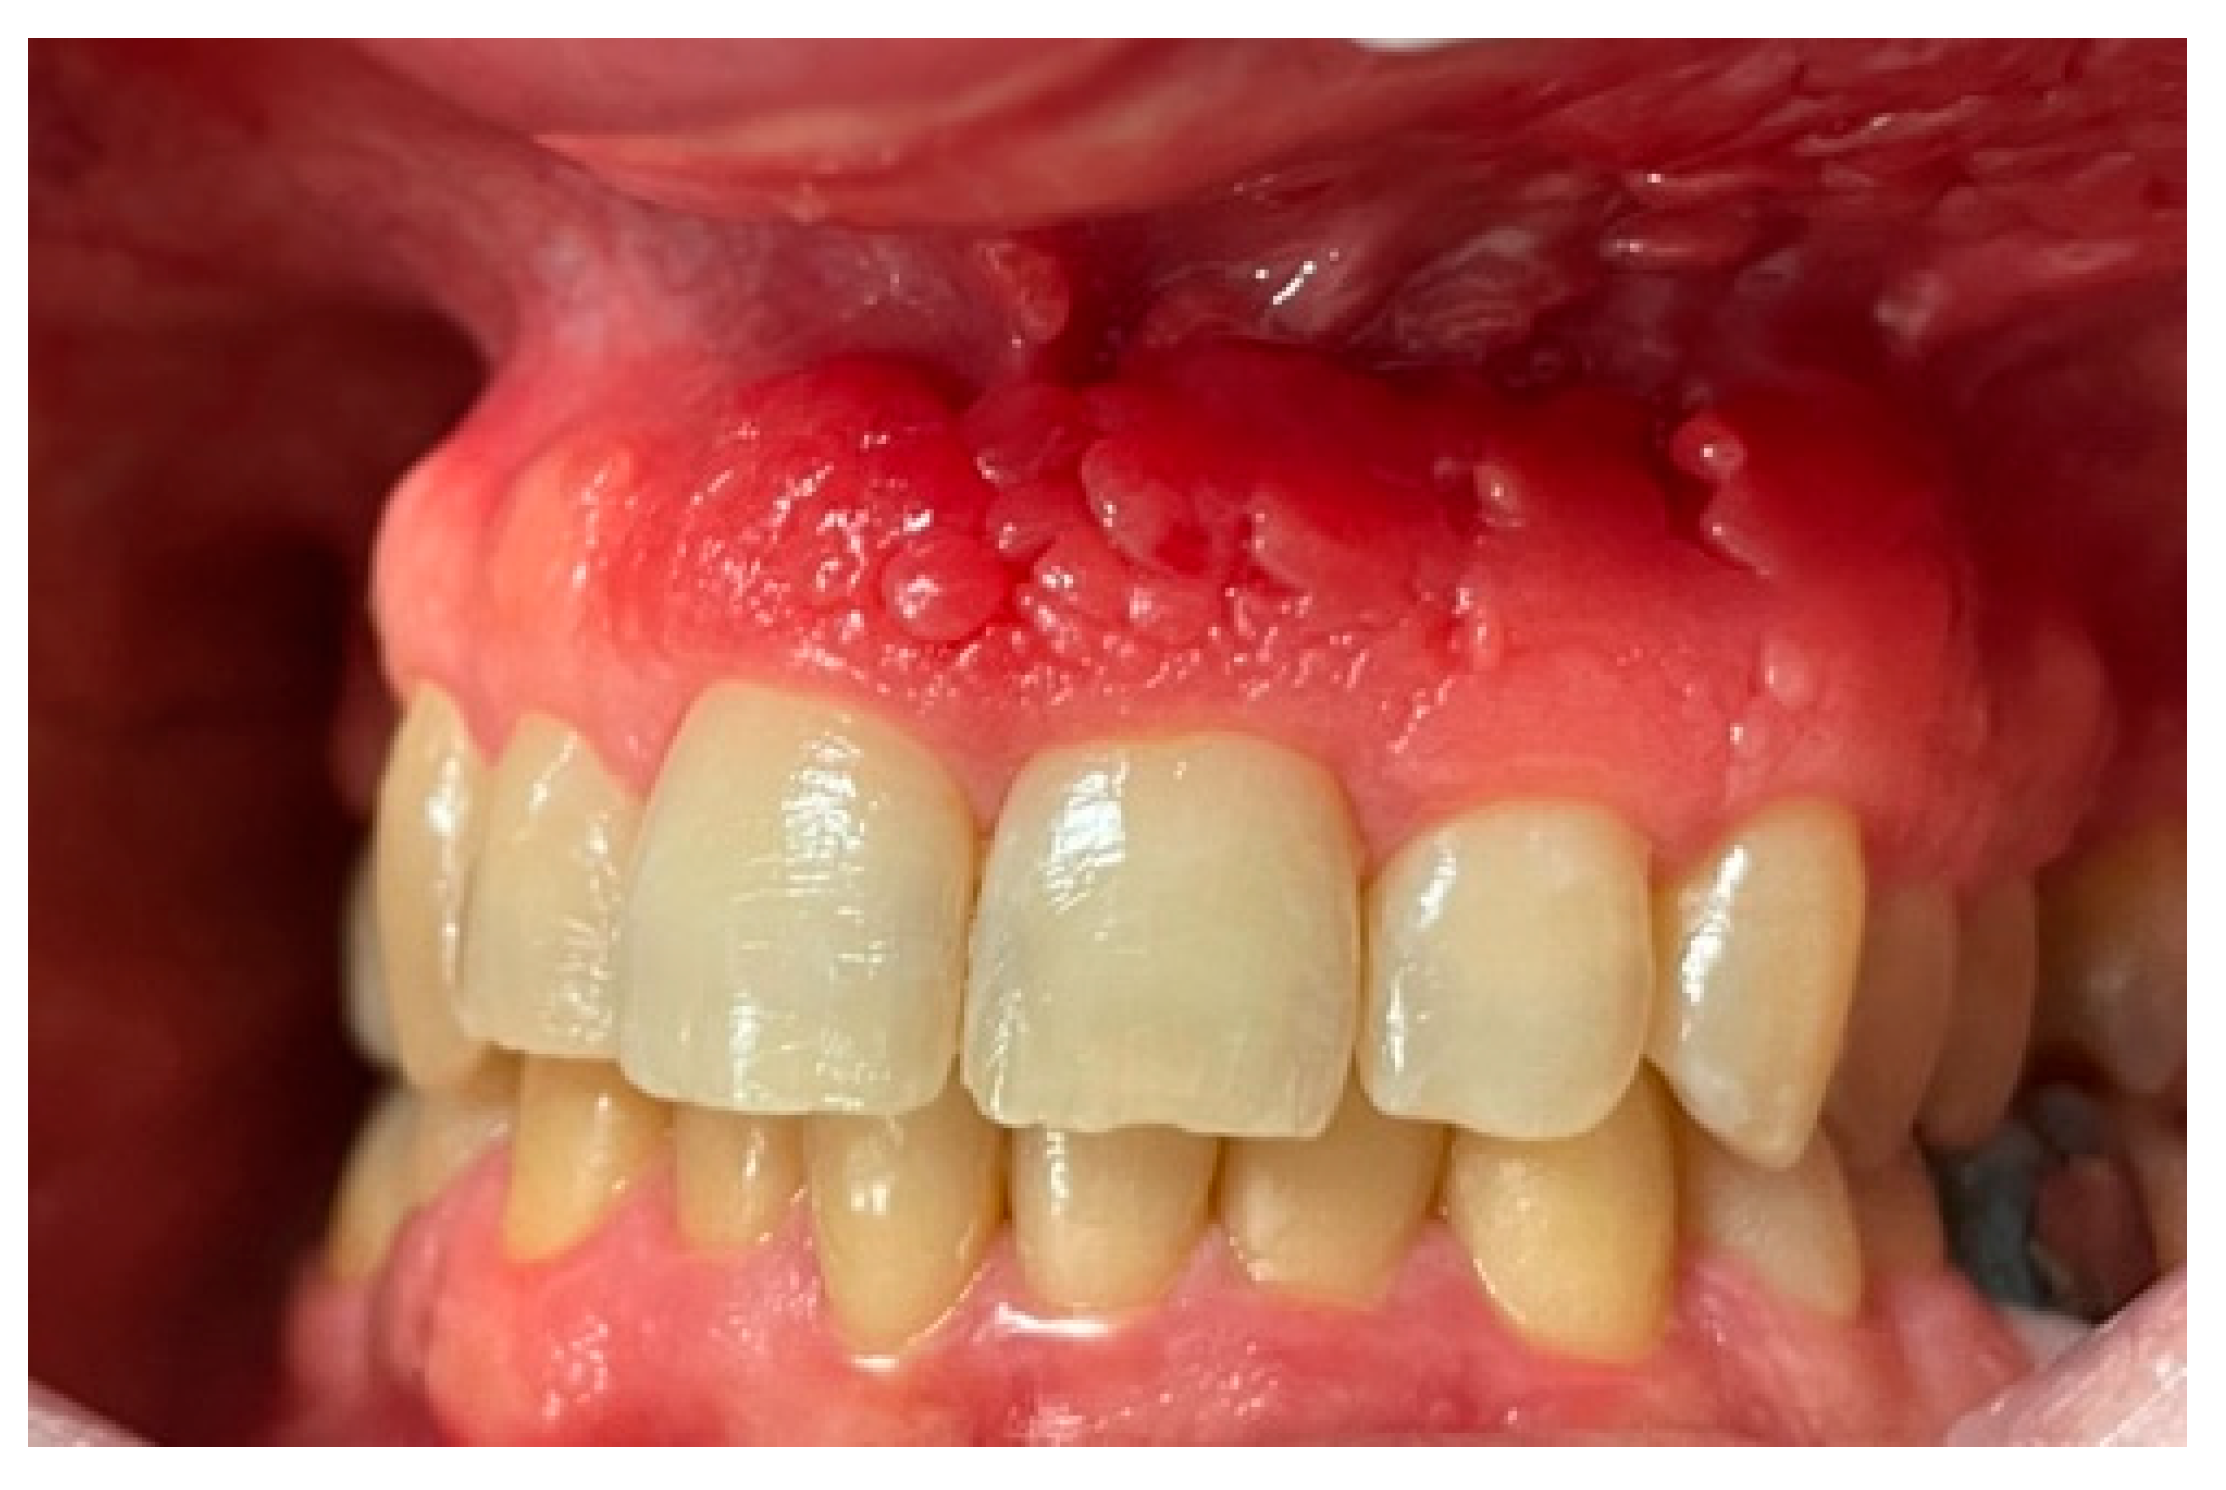

Gingia keratinizată este porțiunea fermă, roz deschis, bine fixată de os, care înconjoară dinții și implanturile.

Aceasta diferă de mucoasa mobilă, care este mai subțire și mai sensibilă.

O gingie keratinizată insuficientă poate duce la:

• inflamație cronică

• disconfort la periaj

• retracții gingivale

• risc crescut de periimplantită